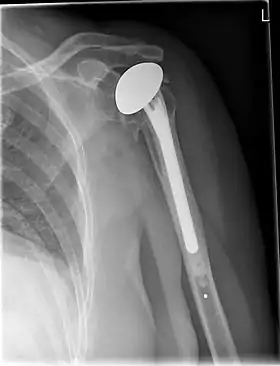

![]() X-ray of a shoulder prosthesis | |

Various materials can be used to make prostheses, however the majority consist of a metal ball that rotates within a polyethylene (plastic) socket. The metal ball takes the place of the patient's humeral head and is anchored via a stem, which is inserted down the shaft of the humerus. The plastic socket is placed over the patient's glenoid and is typically secured to the surrounding bone via cement.[9]